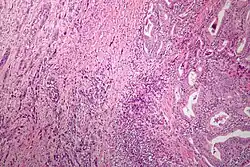

Microscopic image of anaplastic thyroid carcinoma. H&E stain. | |

Anaplastic tumors have a high mitotic rate and frequently invades the local blood and lymphatic vessels.[5] Cellular death is frequently visualized on microscopic images.[2] The presence of regionally swollen lymph nodes in older patients in whom needle aspiration biopsy reveals characteristic vesicular appearance of the nuclei supports a diagnosis of anaplastic carcinoma. Microscopic images of ATC usually show inflammatory cells from the immune system such as T cells and macrophages.[2]

On immunohistochemistry testing, ATC is usually positive for the keratin, p53, and PAX8 proteins and is negative for thyroid transcription factor-1, thyroglobulin, and calcitonin.[2] ATC cells demonstrate high levels of PD-L1 expression.[2] BRAF and TERT mutations are seen more commonly in ATC than in differentiated thyroid cancer.[2]